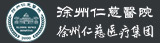

前不久,安徽一名姓刘的男性患者,在结束了一天的工作之后回到家中,身体非常疲惫,因孩子吵闹,一气之下一拳打到墙上,随即右手出现肿胀,疼痛,但他未重视。第二天早上醒来后,刘先生发现自己右手肿胀更加明显,疼得受不了,便到家附近的医院就诊。在医院拍片显示其右手第三、四掌骨颈骨折,断端移位。

术前

熊医生介绍,刘先生术前右手不能握拳,伸不直,伸屈都有影响,术后功能基本恢复正常。